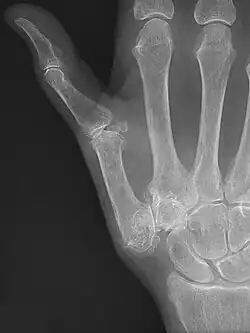

![]() Imagen radiográfica que muestra signos de artrosis de la articulación trapeciometacarpiana. | ||

La rizartrosis, también conocida como artrosis del pulgar[4] u osteoartritis trapeciometacarpiana, es un tipo de artrosis que afecta a la articulación trapecio-metacarpiana. Esta articulación une el primer metacarpo del dedo pulgar con el hueso trapecio del carpo. La rizartrosis se produce cuando el cartílago articular que conecta estas dos estructuras se desgasta, a menudo provocando dolor, rigidez y limitación del movimiento.[1][5] Está estrechamente relacionada con la obesidad y suele desarrollarse en edades avanzadas, siendo mucho más frecuente en mujeres que en hombres. Además, es el segundo tipo de artrosis más común en la mano después de la artrosis de las articulaciones interfalángicas. Su síntoma más común es dolor en la base del pulgar que aumenta con la realización de movimientos del mismo, especialmente si estos implican el uso de fuerza, como el movimiento de pinza.[3] Su tratamiento más común consiste en el uso de fisioterapia, la colocación de férulas y la inyección de corticoides; siendo la cirugía el último recurso en pacientes cuya sintomatología no mejora con el tratamiento conservador.[3]